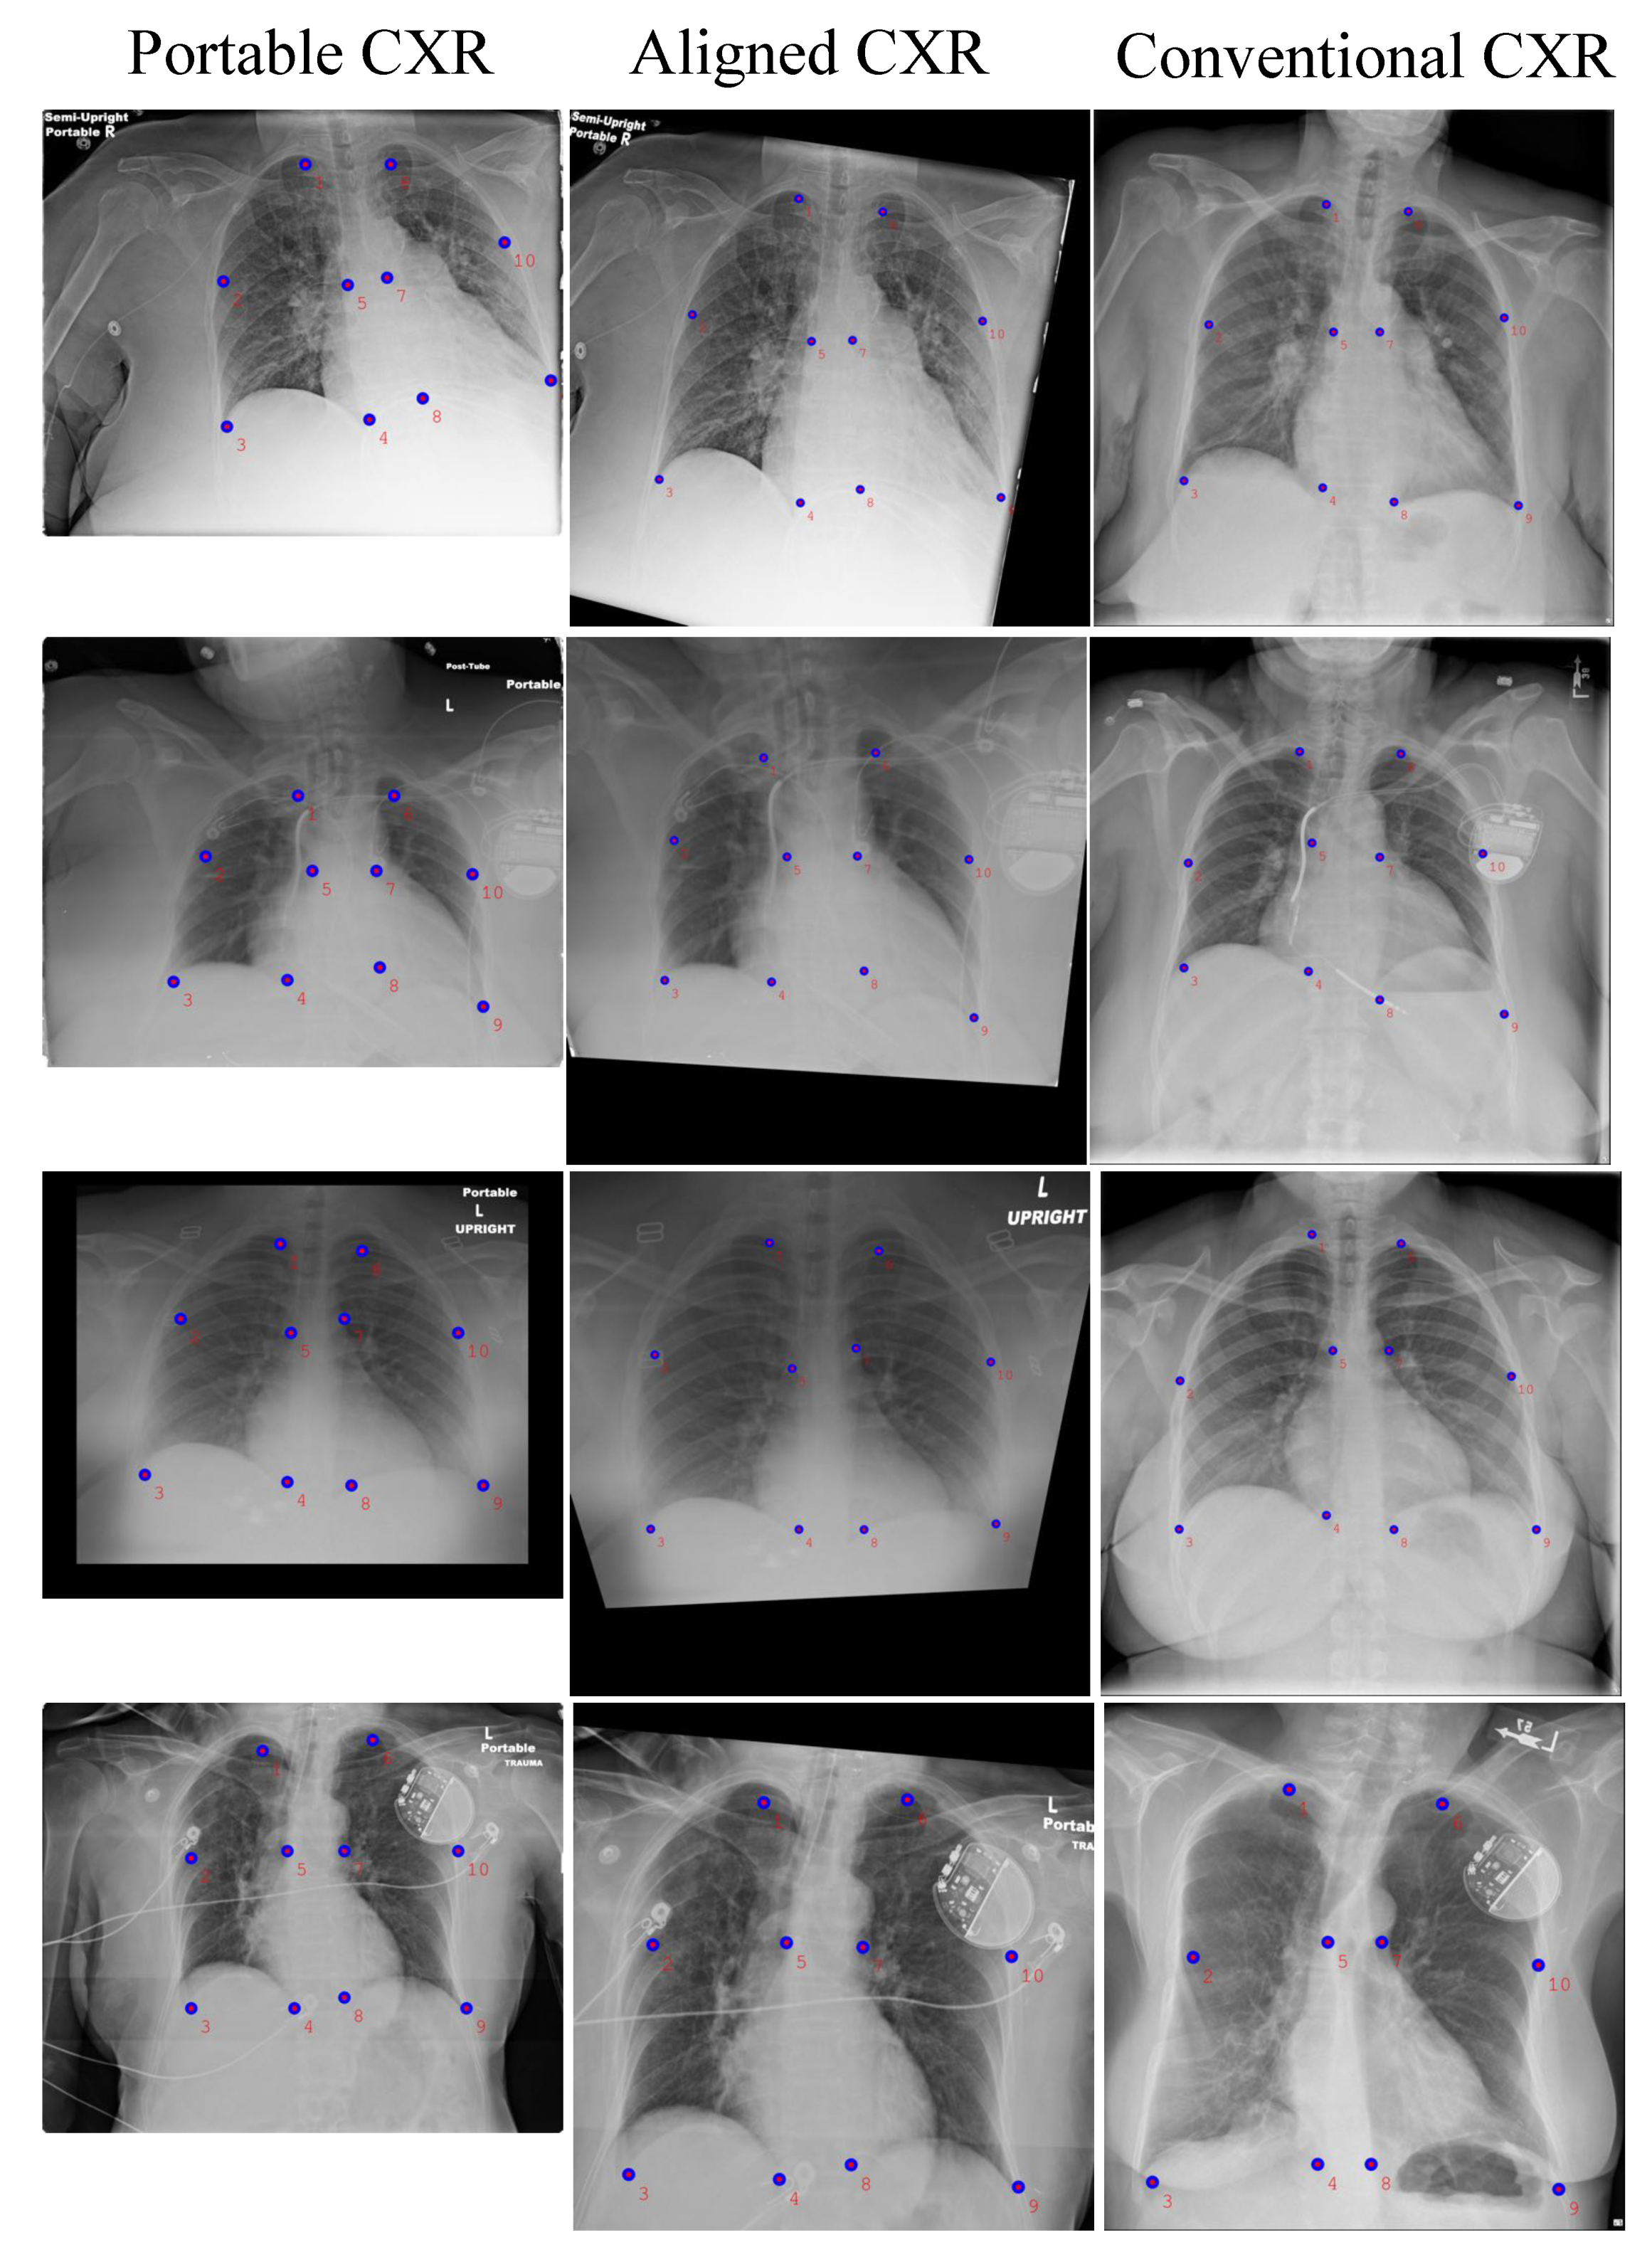

- Secondly, we introduce a new deep learning-based approach to align a subject-pairs dataset to obtain pixel-pairs dataset. In order to learn the knowledge correlation between two different domains, it is important to have a pixel-wise pair dataset. Thus, alignment is an important step that helps to perform knowledge transferring from the source domain to target domain.

3.1. Portable Radiograph Alignment

4.3.1. CXR Alignment Network

| Portable CXR vs. Conventional CXR | Aligned CXR vs. Conventional CXR | |

|---|---|---|

| Left Lung | 203.03 | 42.02 |

| Right Lung | 239.31 | 38.86 |

| Entire CXR | 221.17 | 40.44 |